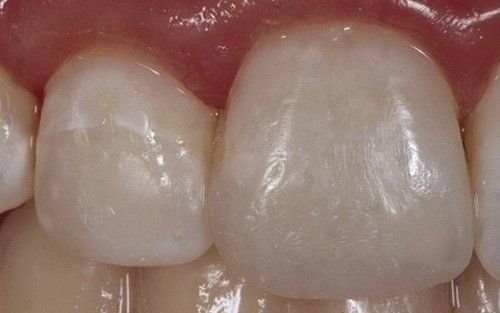

I denti da latte traumatizzati più spesso vanno incontro a necrosi con conseguente cambiamento di colore, divenendo grigiastri, segno della morte delle cellule della polpa dentaria. In altre occasioni, il dente può fratturarsi in maniera più o meno ampia: se il frammento viene ritrovato, potrà essere re-incollato in maniera invisibile, oppure verrà ricostruito con i materiali compositi.